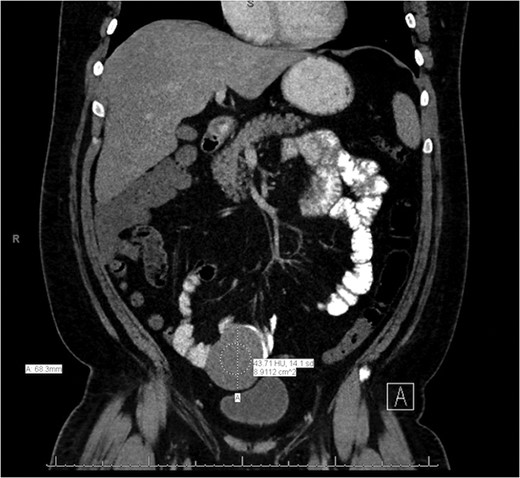

A CT of the abdomen and pelvis without contrast was obtained on admission and revealed a 7 × 7.6 cm2 mass with CT attenuation of 37.34 Hounsfield units within the anterior left midpelvis. It appeared to be inseparable along its superior aspect from a loop of bowel, and it was felt to possibly be an unusual diverticulum. The patient was given intravenous fluids and one unit of packed red blood cells for his symptomatic anemia with continued rectal bleeding. He was also empirically started on Cipro and Flagyl for possible infection coverage. GI was consulted and the patient was taken for an EGD and colonoscopy; however, both were negative for any acute pathology.

General surgery was then consulted for further recommendations. A CT of the abdomen and pelvis with contrast was performed and demonstrated a 7.2 × 6.8 × 6.1 cm3 lesion arising from the mid-to-distal small bowel loop with no evidence of significant enhancement. It appeared mobile within the mesentery of the small bowel when compared to previous imaging (Figs. 1 and 2). The patient had continued to bleed and required transfusion with five units of packed red blood cells; therefore, it was decided to take the patient to the operating room for a diagnostic laparoscopy.

Coronal slice of the CT of the abdomen/pelvis demonstrating a lesion arising from the mid-to-distal small bowel.